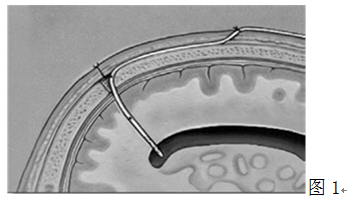

有根据传感器放置位置的不同,可将颅内压监测分为脑室内(图1)、脑实质内(图2)硬膜下(图3)和硬膜外测压(图4)。按其准确性和可行性依次排序为:脑室内导管>脑实质内光纤传感器>硬膜下传感器>硬膜外传感器。室内压力监测:是目前测量颅内压的金标准。